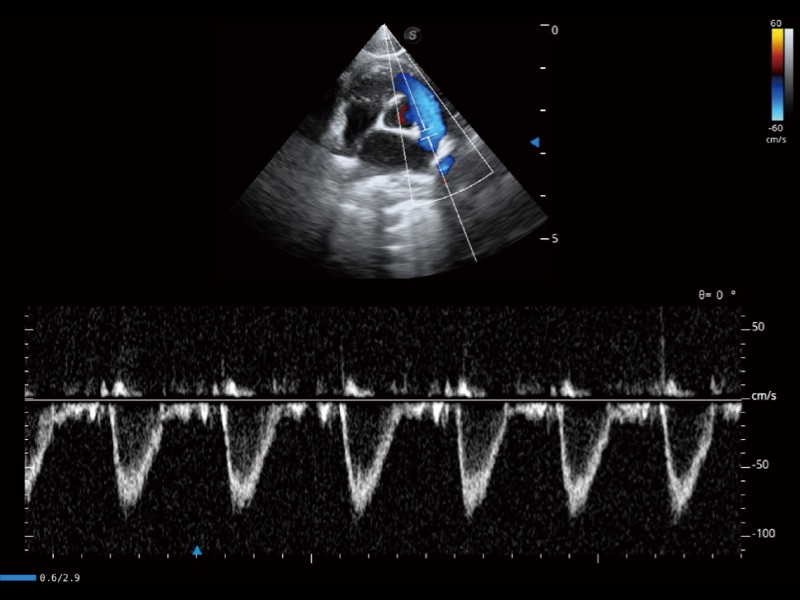

通過(guò)360度任意調(diào)節(jié)3條M型取樣線(xiàn),在同一心動(dòng)周期上觀(guān)察心臟不同位置的運(yùn)動(dòng)曲線(xiàn),得到準(zhǔn)確的心功能測(cè)量數(shù)據(jù),有效評(píng)估心肌運(yùn)動(dòng)及左心室功能。